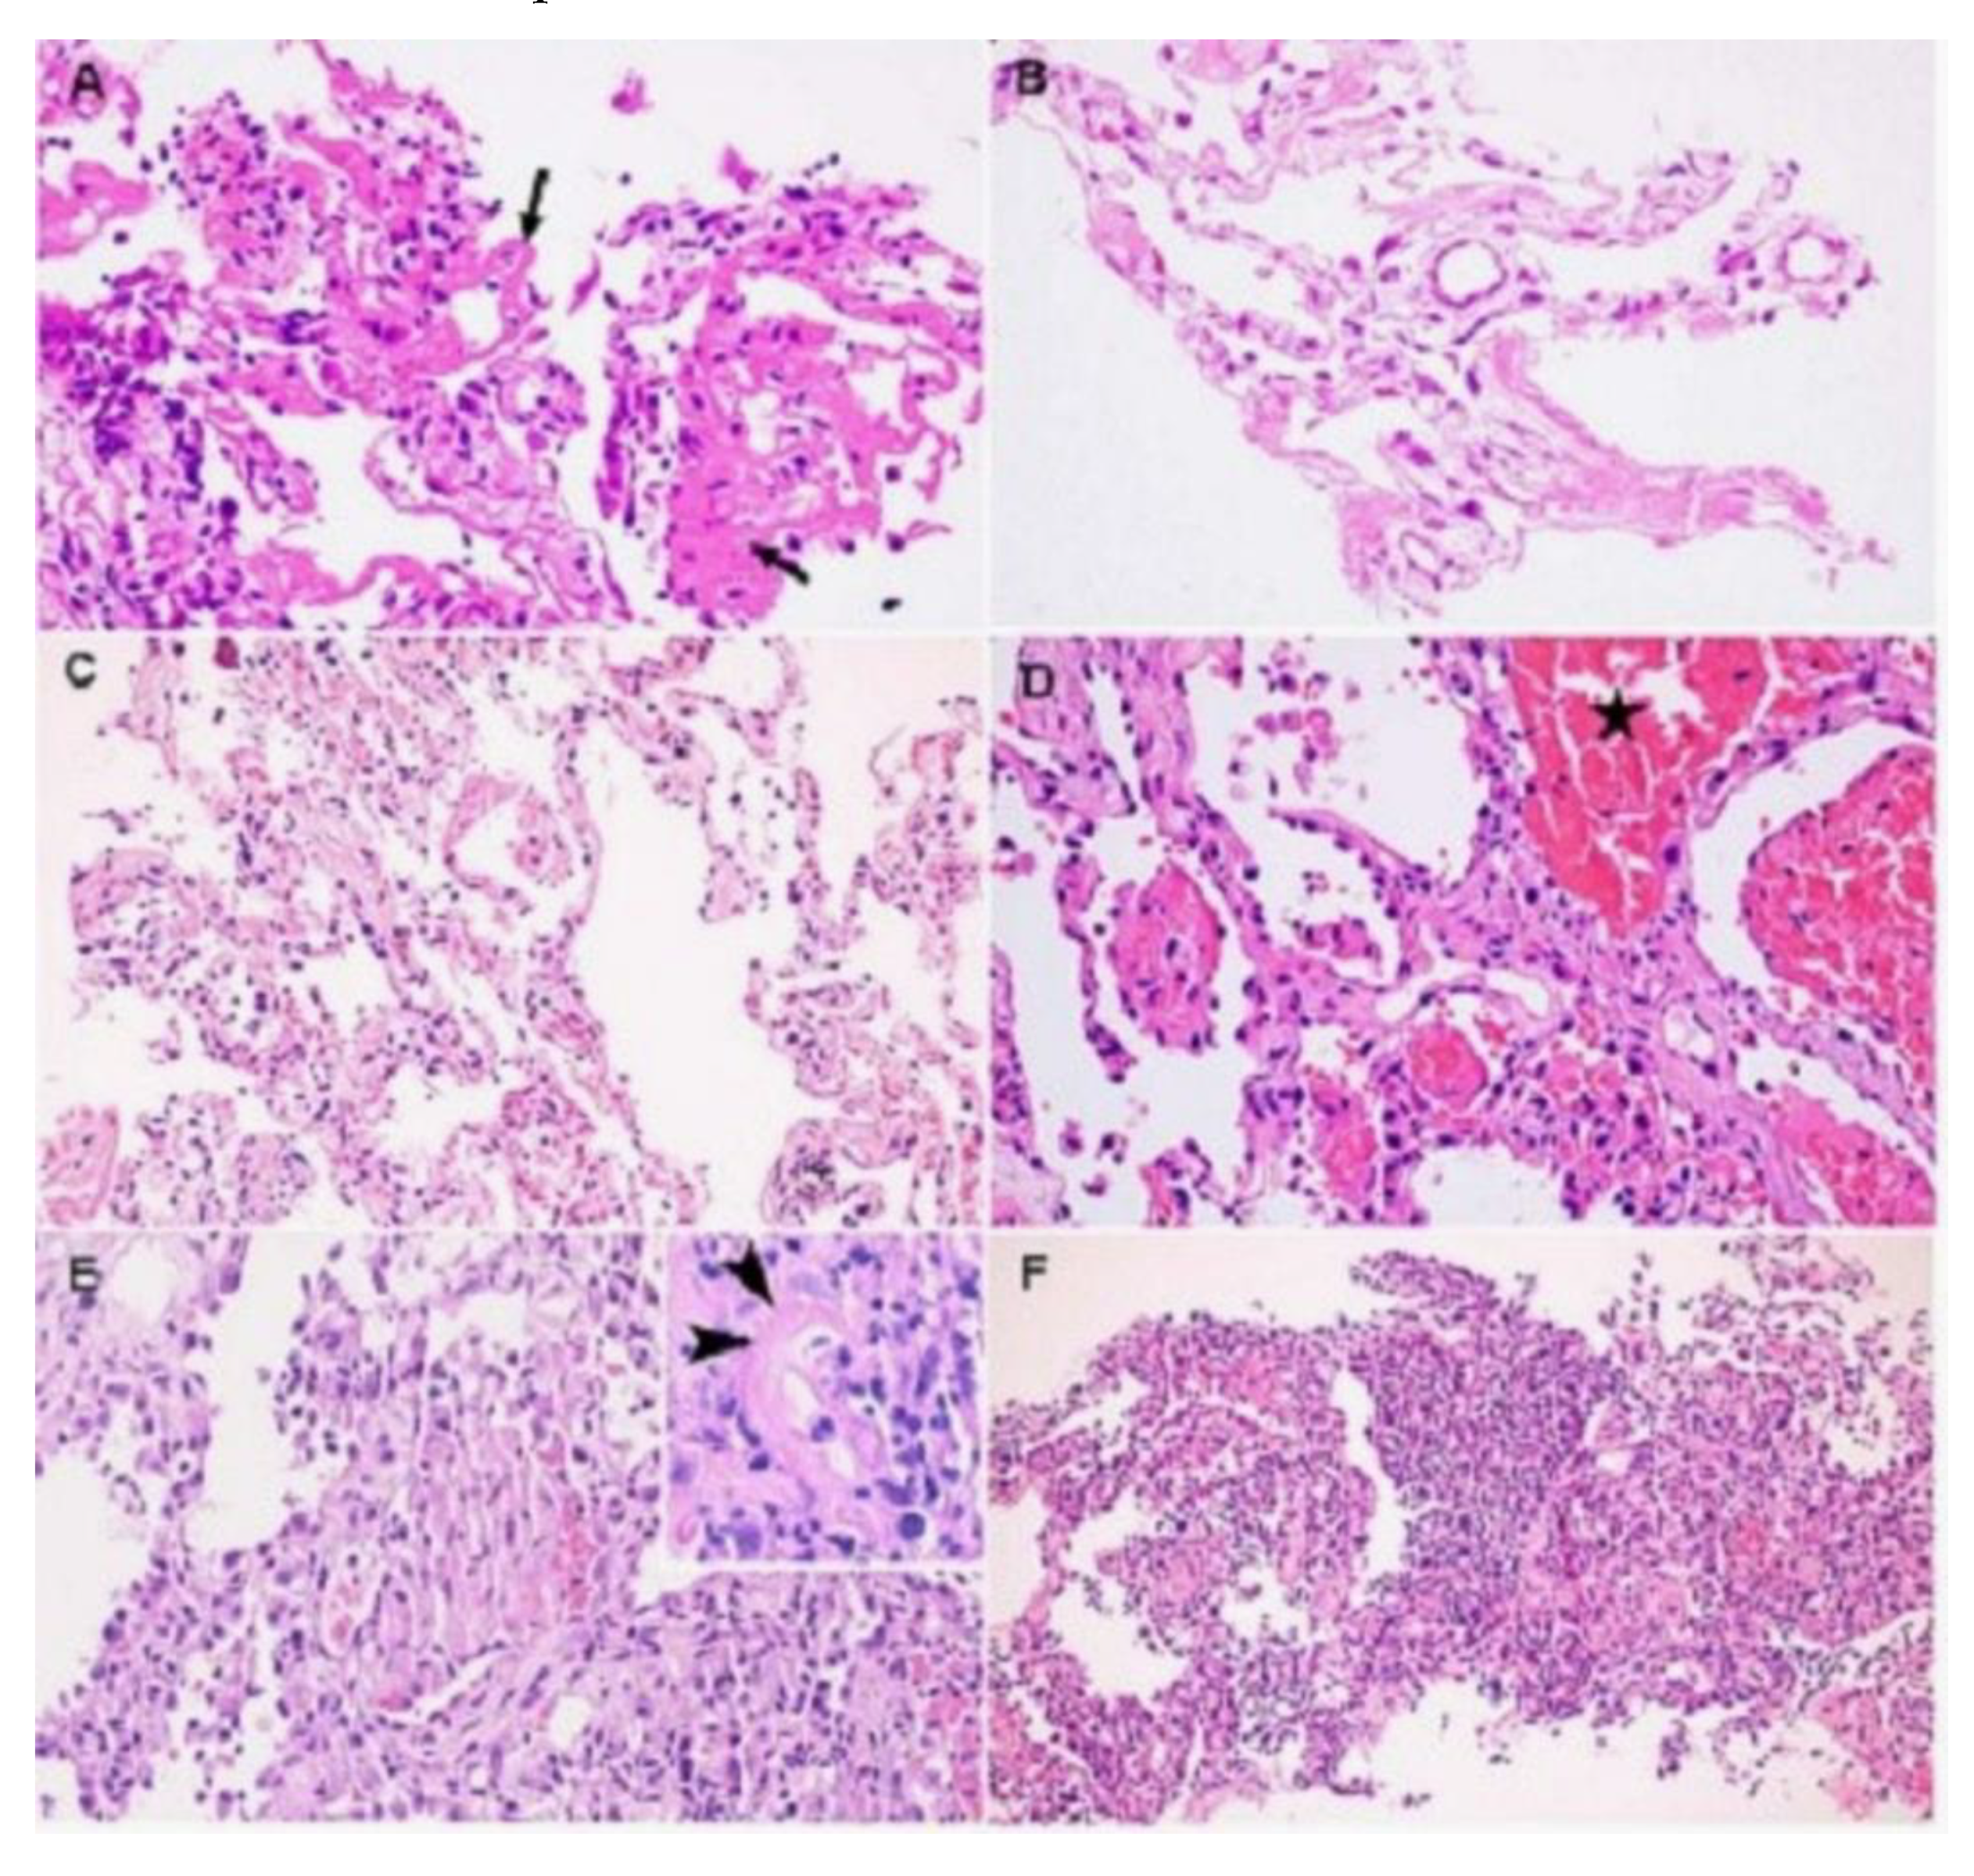

- Histopathology

- Respiratory system